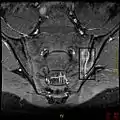

T1-weighted MRI with fat suppression after administration of gadolinium contrast showing sacroiliitis in a person with ankylosing spondylitis